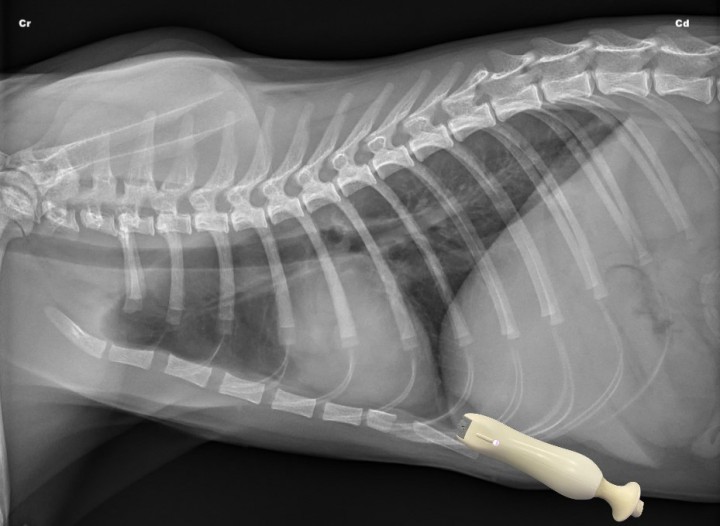

- Dorsocaudal (DC) bilateral: El transductor debe colocarse horizontalmente entre el 7º y 8º espacio intercostal de ambos hemitórax en su tercio dorsal (Fig. 1).[ Lisciandro G: Abdominal and thoracic focused assessment with sonography for trauma, triage, and monitoring in small animals. J Vet Emerg Crit Care 2011; 21(2): 104-122. [PubMed] ] Se examina de forma estática, colocando la sonda con el haz en plano longitudinal al paciente (transversal a las costillas) para maximizar el contacto del transductor con el borde pulmonar. Son los cuadrantes de elección para detectar neumotórax y patología pulmonar.[ Lisciandro G: Abdominal and thoracic focused assessment with sonography for trauma, triage, and monitoring in small animals. J Vet Emerg Crit Care 2011; 21(2): 104-122. [PubMed] , Boysen S, Lisciandro G: The Use of ultrasound for dogs and cats in the emergency room. AFAST and TFAST. Vet Clin Small Anim 2013; 43: 773-797. [PubMed] ]

<p>Radiografía lateral derecha de un gato sano en la que se observa la posición del transductor para valorar el cuadrante dorsocaudal (DC) de la T-FAST. Cr: craneal; Cd: caudal.</p>

Radiografía lateral derecha de un gato sano en la que se observa la posición del transductor para valorar el cuadrante dorsocaudal (DC) de la T-FAST. Cr: craneal; Cd: caudal.